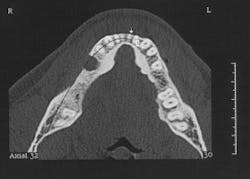

Figure 2 - CT scan showing large bone defect

Figure 2a - CT scan showing large bone defect